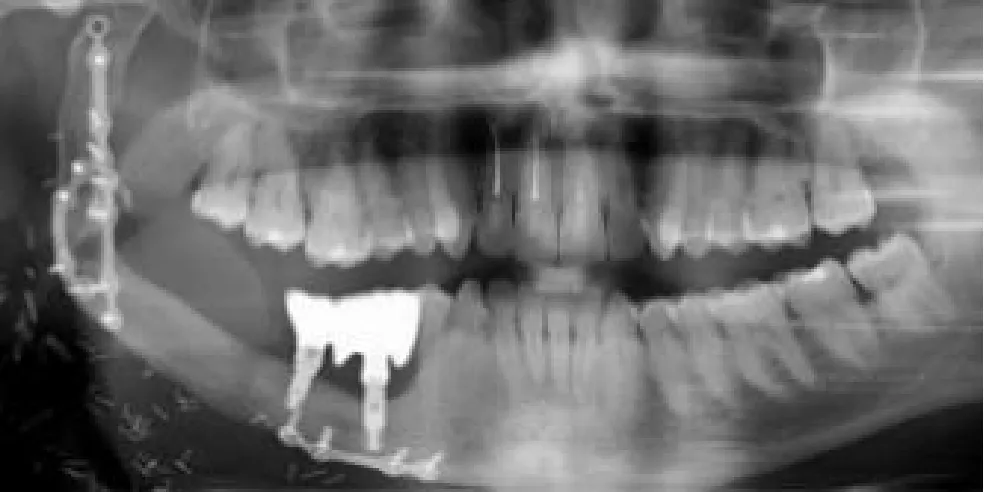

| Mandibular right body and ramus ameloblastoma | Segmental mandibulectomy | Fibula flap | sCAIS | 2 flap, 1 failed | Fixed screw retained | ![]() |

| Right mandibular body epidermoid carcinoma | Segmental mandibulectomy and neck dissection | Double-barrel fibula flap | dCAIS | 3 flap | Fixed screw retained | ![]() |

| Left mandibular body epidermoid carcinoma | Segmental mandibulectomy and Neck dissection | Iliac crest free flap | dCAIS | 2 flap | Fixed screw retained | ![]() |

| Left mandibular body ameloblastoma | Segmental mandibulectomy | Fibula flap | dCAIS | 4 flap | Fixed screw retained | ![]() |

| Right mandibular body ameloblastoma | Segmental mandibulectomy | Fibula flap | dCAIS and freehand | 3 flap | Fixed screw retained | ![]() |

| Hard palate adenoid cystic carcinoma | Central maxillectomy | Radial forearm flap | dCAIS and sCAIS | 5 Mx | Fixed screw retained | ![]() |

| Left maxilla tuberosity adenocarcinoma | IIb Brown maxillectomy | Iliac crest free flap | dCAIS and sCAIS | 3 flap | Fixed screw retained | ![]() |

| Left mandibular body epidermoid carcinoma | Segmental mandibulectomy and Neck dissection | Double-barrel fibula flap + 70 Gy | dCAIS and sCAIS | 3 flap | Fixed screw retained (Pending) | ![]() |

| Left mandibular body epidermoide carcinoma | Segmental mandibulectomy and Neck dissection | Fibula flap | dCAIS and sCAIS | 3 flap | Fixed screw retained (pending) | ![]() |

| Right hemitongue epidermoid carcinoma | Hemiglosectomy, bilateral neck dissection | Alt+ Vastus Lateralis Flap + 70 Gy | dCAIS | 6 mx | Fixed screw retained (pending) | ![]() |

| Left hemimandible ameloblastoma | Segmental mandibulectomy | Failed Fibula flap and pectoralis major | sCAIS | 5 mx | Fixed screw retained (pending) | ![]() |